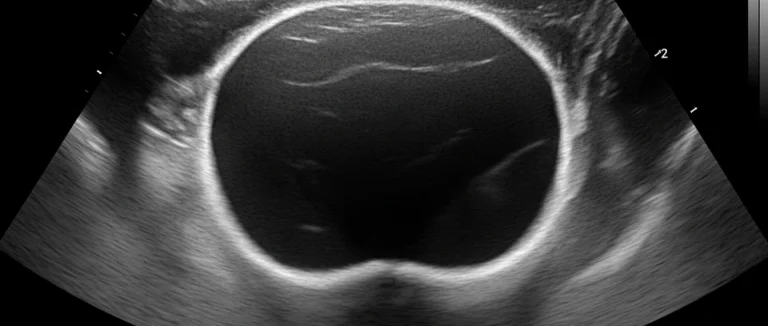

- УЗИ мочевого пузыря — позволяет оценить объём, стенки и остаточный объём после мочеиспускания.

| УЗИ | Оценка анатомии | Быстро, безболезненно |